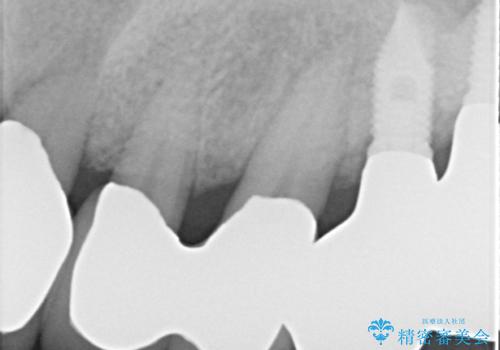

歯周病におかされた前歯の再建治療

- 歯周病により欠損が生じた歯槽骨、まずは再生治療をおこなう

→治癒後、確定外科を行い完全に歯周ポケットを除去し、最終的に歯周補綴をおこなう